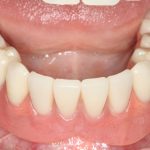

К счастью, уже через 6 недель после операции вдруг выяснилось, что ничего исправлять не нужно:

Фактически, нам осталось лишь дождаться приемлемого уровня остеоинтеграции имплантатов,  — примерно 2-3 месяца, — и можно переходить к постоянному протезированию.

Через три месяца мы сняли коронки с имплантатов, чтобы оценить качество формирования десневого контура:

С этого момента можно перестать переживать — десневой контур сформировался правильно, мы получили достаточный объём и качество окружающей платформу имплантата десны. Можно приступать к изготовлению постоянной протетики. Подрядчиком стала зуботехническая лаборатория French Creative, одна из топовых лабораторий Москвы.

И вот, в жизни Марии наступил долгожданный день — окончательная фиксация керамических коронок на установленные имплантаты:

При этом, она ни дня не оставалась без зубов, была полностью социализирована и жила обычной жизнью. Спустя 5 месяцев после удаления, поставленную Марией клиническую задачу можно считать решёной. Но это с её точки зрения. С нашей же, всё самое интересное только начинается.